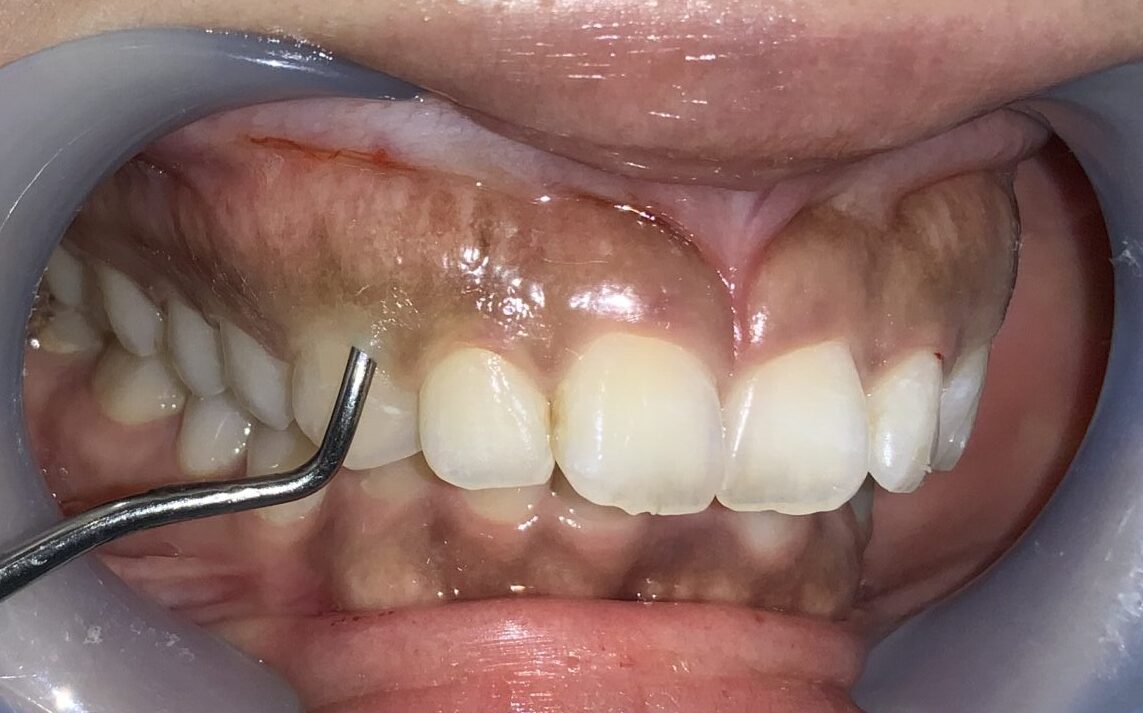

まずは歯ぐきのかぶり具合、歯ぐきの厚み、歯槽骨の状態、歯ぐきの切除範囲の検査からです。

このくらいかぶっていますから、綺麗に切除できます。

反対側の前歯です。

こちらもたくさんかぶっています。歯槽骨のとがった部分もあり、ざらざらした面もありますから、歯槽骨整形も同時に行う必要がありそうです。